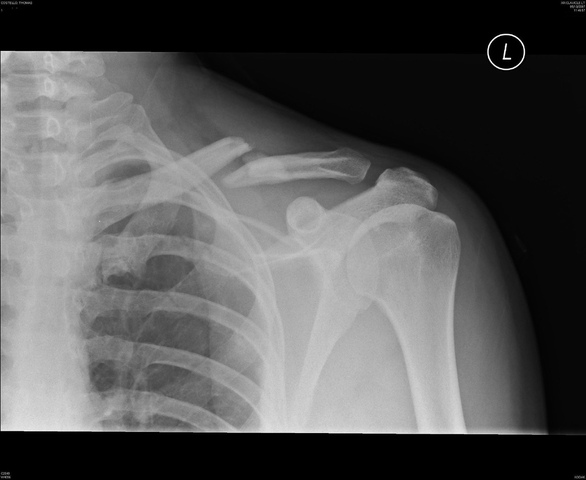

when i was 2 i was playin on 2 chairs and fell off and broke my coller bone all i needed was a cast and sling.Warning: Do not jump on chairs.